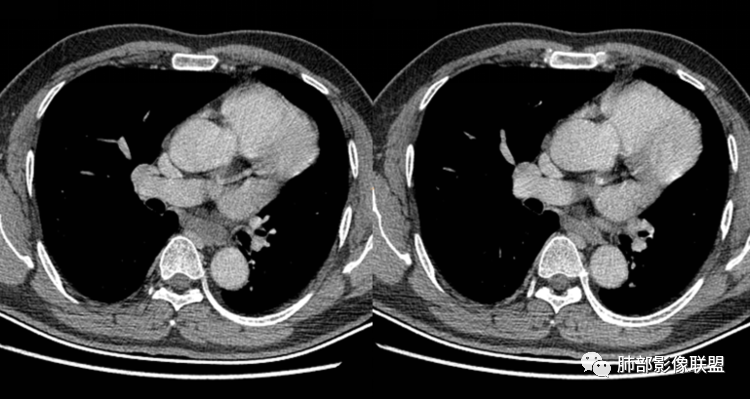

男性,43岁,体检发现后纵隔占位,边缘光整,CT示密度均匀,周围组织受压移位,无钙化囊变及脂肪组织,增强未见明显强化。MRI:T1示肿块信号较肌肉高,T2不均匀高信号。考虑为良性病变,第一是神经节细胞瘤,其次是支气管源性囊肿。

中年男性,无症状,后纵隔肿块,长径大矢状位于横径,质地偏软,塑形,等t1稍长t2,比较均质,增强轻微强化,与脊柱,主动脉,食管脂肪间隙存在,部分层面与脊柱相贴,骨质无改变,周围无肿大淋巴结,考虑神经源性肿瘤,节细胞神经瘤可能大,鉴别心包斜窦,淋巴瘤,淋巴管囊肿。

后纵隔占位,椭圆形,边缘不规则,CT低密度,MRI长稍长T1稍长T2信号,增强扫描未见强化,支气管受压。囊性病变,考虑支气管囊肿(常见,T1WI稍低“比水高”T2WI稍高,可能与其内含有粘液或蛋白有关);鉴别淋巴管囊肿(更软塑性性更大,接近纯水MRI信号长T1长T2,受周围挤压更明显,变形。);神经节细胞瘤瘤(增强可有轻度渐进性强化,也可不强化,关键是不常见),还有就是神经源性囊肿与肠源性性囊肿。

秦化君:

后纵隔占位;食道向右侧推移,病变质软,CT平扫密度均匀,边缘清晰光整,MRI 稍长T1,长T2高,脂肪抑制高信号。考虑纵隔良性囊性占位。先考虑支气管囊肿。其它类囊肿待除外。